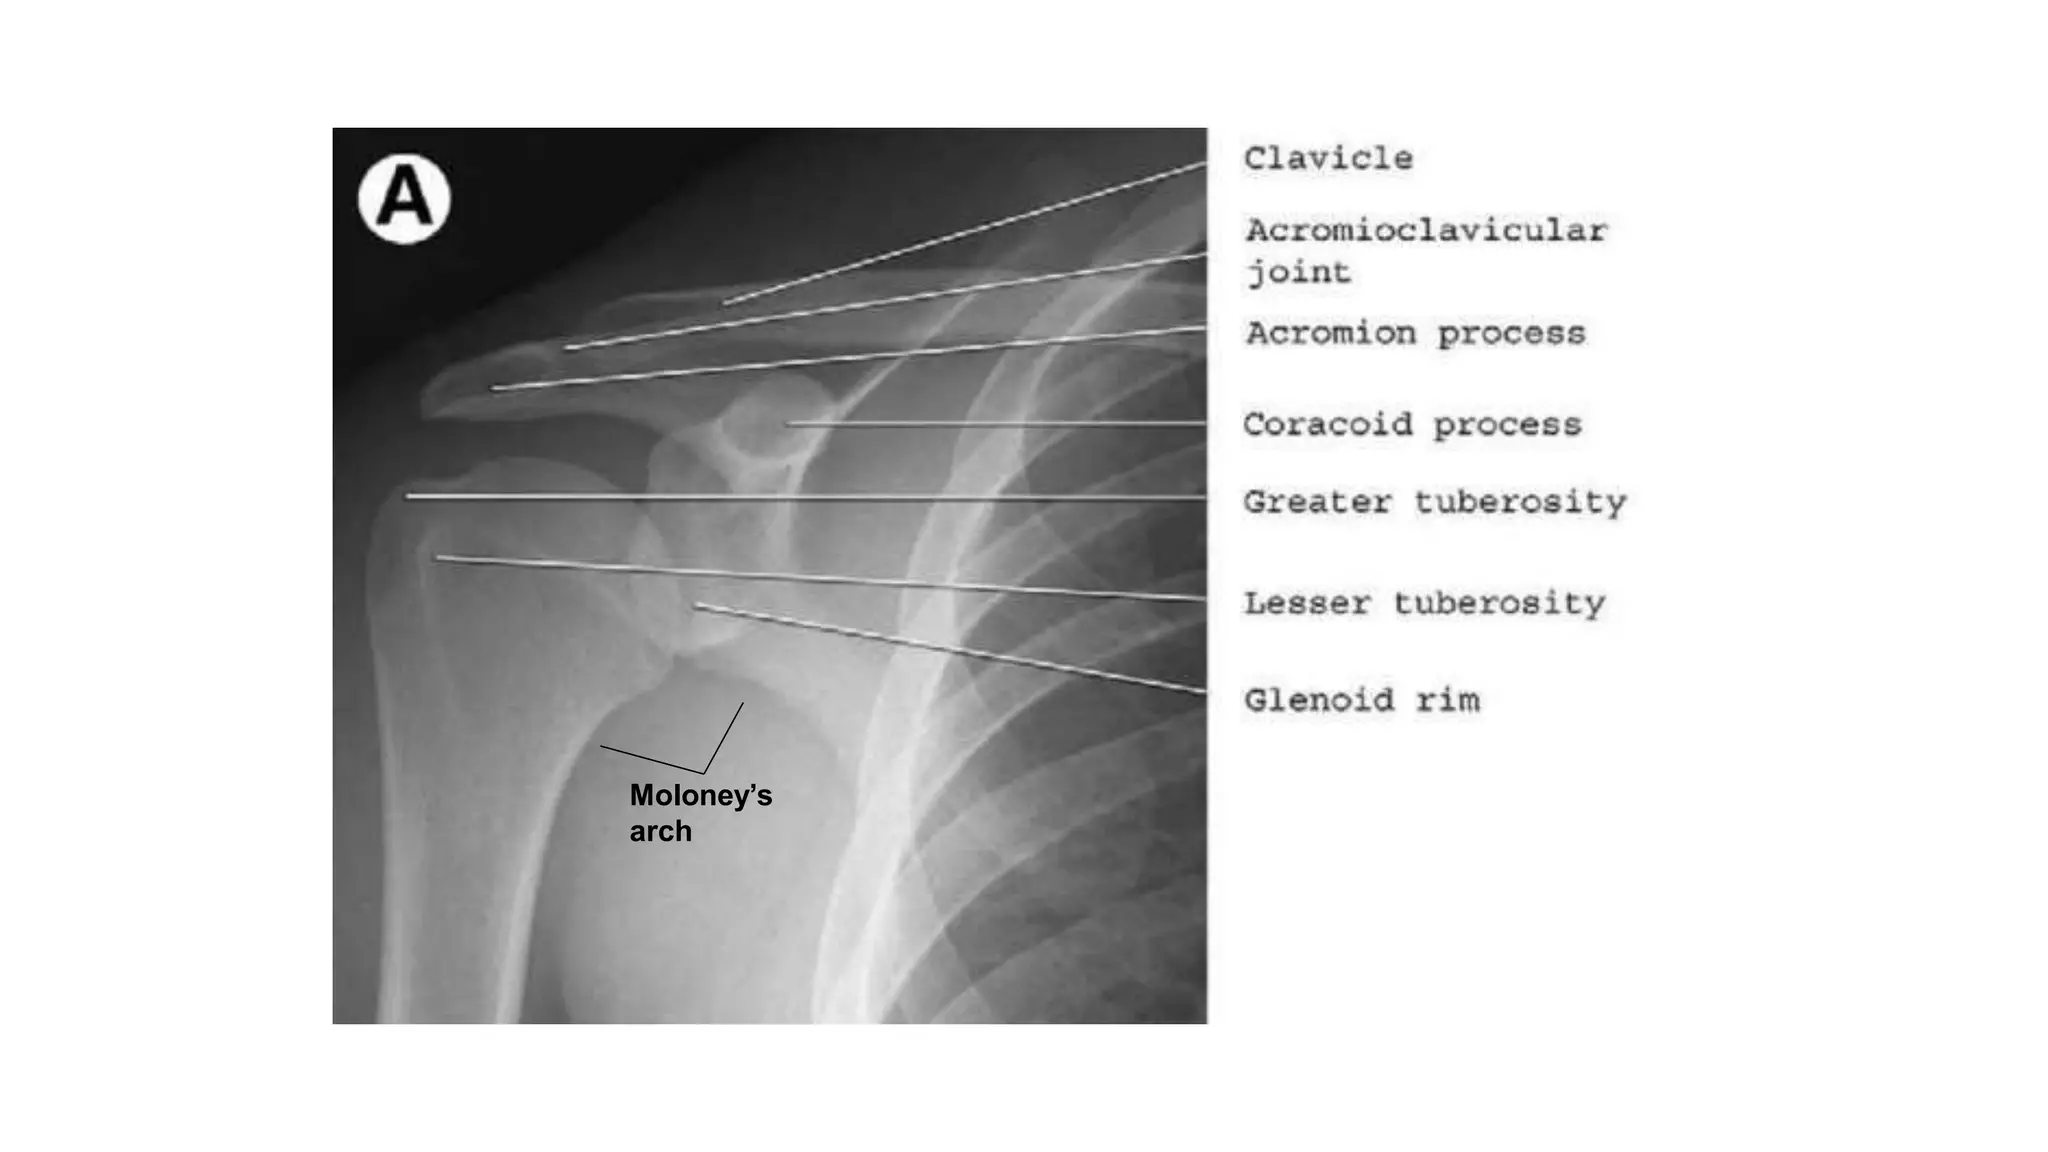

1. ANTEROPOSTERIOR (AP) VIEW

• Two AP projections:

• With the arm in external rotation: , the humeral head has the appearance of an Indian axe.

• With the arm in internal rotation: the humeral head has the appearance of an ice-cream cone.

• Since the glenohumeral joint is normally anatomically tilted 35–40 degree anteriorly,

this projection results in overlap of the glenoid and humeral head.

SHOULDER RADIOGRAPH PROJECTIONS

• The AP projection is usually obtained with the patient in the upright or supine position

and with the coronal plane of the body parallel to the cassette.

• The beam is directed in a true AP direction relative to the body.

• This results in slight overlap of the glenoid rim and the humeral head as the glenohumeral joint

is tilted anteriorly approximately 40°.

• The lateral border of the scapula and the medial cortex of the proximal humerus form a gentle, smooth

convex arch, known as scapulohumeral or Moloney’sarch.

The beam is oriented in true AP view to the patient with the arm positioned in either neutral, internal, or external

rotation. The beam is centered on the coracoid process with the blade of the scapula almost parallel to the film.

AP external rotation. There is overlap of the humeral head and the glenoid (ellipse). The anterior (arrow) and posterior

(thick dashes) margins of the glenoid are seen. The greater tuberosity (G) is seen in profile. The acromiohumeral

distance (line) is normal (>7 mm).

AP internal rotation. The humeral head is round in appearance with a smooth posterior contour. The fat along the

subacromial-subdeltoid bursa is seen as a lucent crescent (arrowheads).

Moloney’s

arch